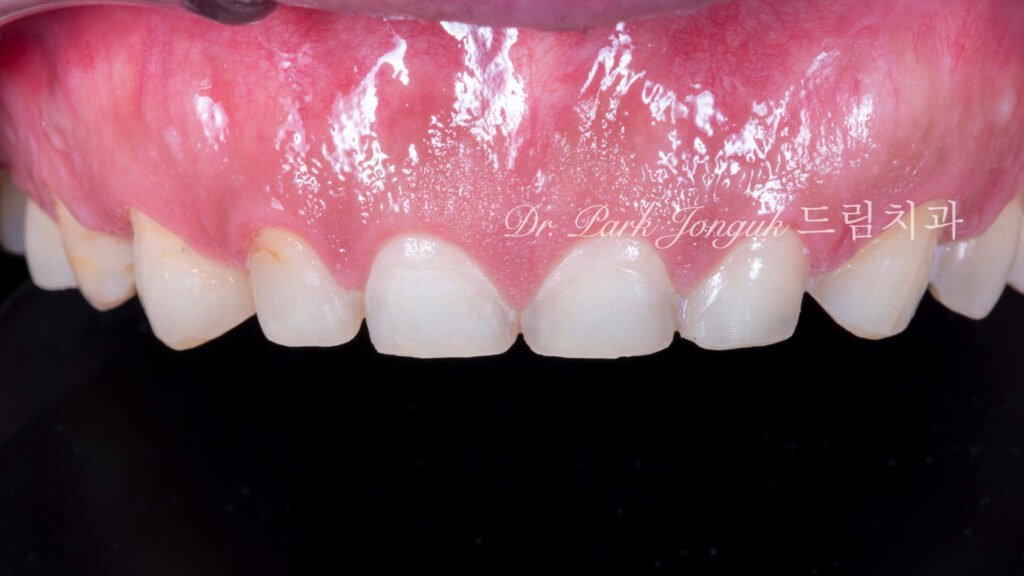

5. 최종 복원: 자연미의 극대화 (사진 6, 7, 8)

5.1 무삭제 라미네이트의 완성

[사진 6, 7, 8 참조] 0%의 삭제율로 완성된 최종 결과물입니다.

- 기능적 보호: 위산에 의해 약해진 치아 표면을 강도 높은 세라믹이 보호막처럼 감싸주어 추가적인 부식을 차단합니다.

- 광학적 재현: 기계로 깎아낸 Monolithic 방식이 아닌, 숙련된 기공사의 **핸드메이드 빌드업(Build-up)**을 통해 자연치 특유의 투명도와 질감을 재현했습니다.

- 심미적 조화: 교정으로 바르게 정렬된 치열 위에 정밀 설계된 라미네이트가 더해져, 부자연스러운 돌출감 없이 조화로운 미소를 완성했습니다.